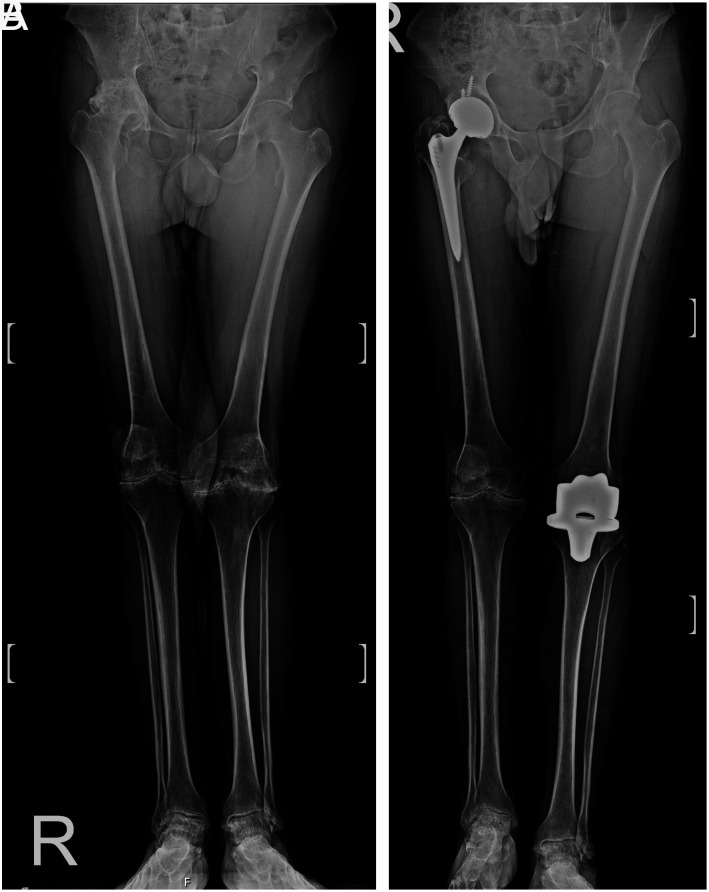

Methods: A retrospective database search identified five patients with severe factor 8 deficiencies who underwent simultaneous hip and knee joint replacement surgery between 2002-2018. Preoperative and postoperative evaluations included Harris Hip Score (HHS), Knee Society Score (KSS), Knee Injury and Osteoarthritis Outcome Score (KOOS), range of motion, flexion contracture (FC), Visual Analog Scale (VAS), hip-knee angle, and leg length discrepancy.

Results: The mean age of the patients was 50.8 years, with a mean follow-up duration of 60 months. Preoperative knee ROM was 55 degrees, improving to 73.8 degrees postoperatively. Preoperative knee FC was 13.7 degrees, improving to 10 degrees postoperatively. HHS increased from 45.6 to 75.7, KSS increased from 36 to 69.3, and KOOS total score increased from 34.4 to 82.7. VAS scores decreased from 6.3 to 1.3. One patient experienced prolonged bleeding and subsequent complications, while the others showed significant improvements.